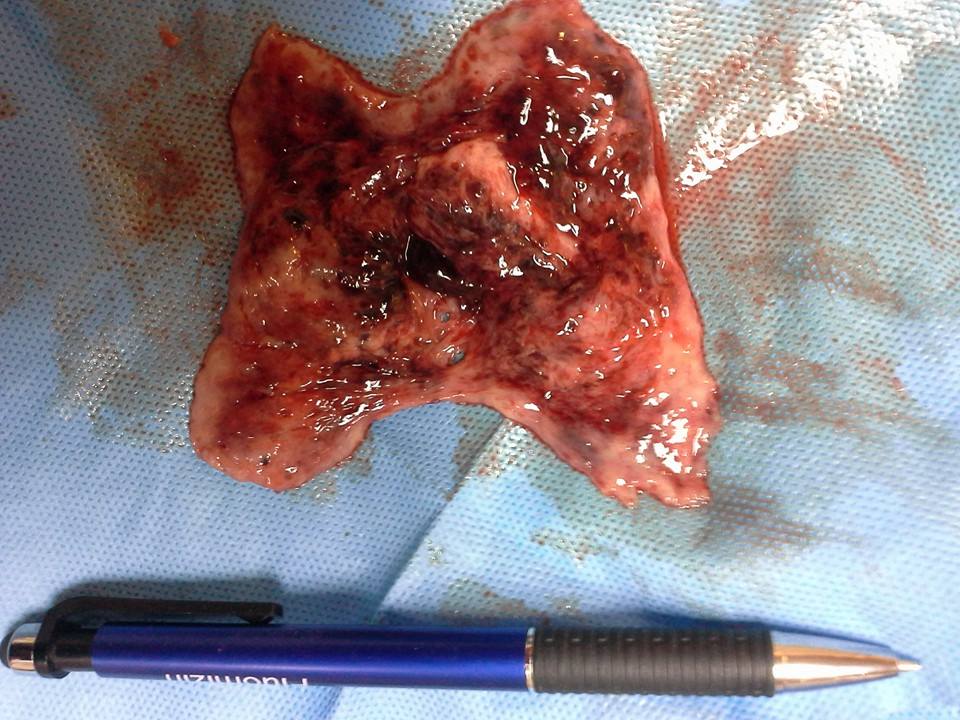

เมื่อวานมีคนไข้อายุ ๔๑+ มาด้วยปวดท้องมีเลือดออก ปวดมากๆจนทนไม่ได้ จู่ๆก็มีชิ้นเนื้อขนาดใหญ่เท่าฝ่ามือ หลุดออกมาทางช่องคลอด พอชิ้นเนื้อหลุดเสร็จเธอก็หายปวดราวคลอดลูก

เธอเป็นโสดไม่มีเพศสัมพันธ์ เธอคิดว่าอ้วน เลยกินยาลดความอ้วนชื่อดังที่ดาราสวยๆคนดังแสดงแบบ....

หมอบอกเธอว่ายานี้มีส่วนผสมที่ออกฤทธิ์แบบฮอร์โมนเพศหญิงด้วย เพราะโฆษณาบอกผิวขาว หน้าท้องแบน ทำนองนี้ ยาไปทำให้เยื่อบุโพรงมดลูกหนาตัวมาก ร่างกายมีการต่อสู้เพื่อไม่ให้กลายเป็นมะเร็งโพรงมดลูก โดยการบีบตัวออก...บุญนะที่บีบออกมาได้...ไม่งั้น???